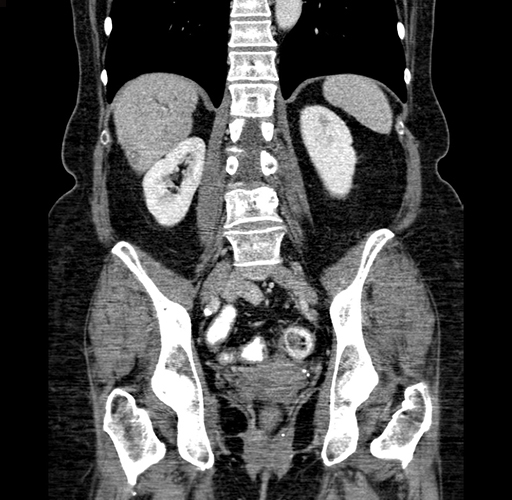

Axial Venous

Coronal Venous